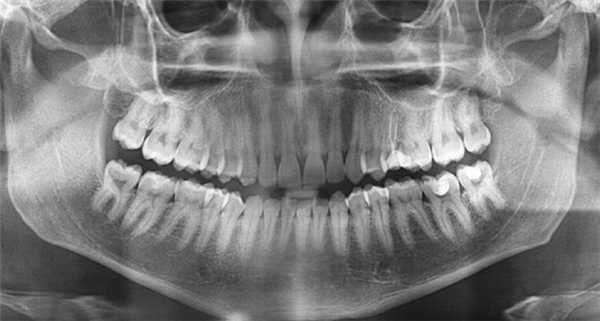

Прямые панорамные рентгенограммы имеют преимущество перед внутриротовыми снимками по богатству деталями изображения костной ткани и твердых тканей зубов. При минимальной лучевой нагрузке они позволяют получить широкий обзор альвеолярного отростка и зубного ряда, облегчают работу рентгенолаборанта и резко сокращают время исследования. На этих снимках хорошо видны полости зуба, корневые каналы, периодонтальные щели, межальвеолярные гребни и костная структура не только альвеолярных отростков, но и тел челюстей. На панорамных рентгенограммах выявляются альвеолярная бухта и нижняя стенка верхнечелюстной пазухи, нижнечелюстной канал и основание нижнечелюстной кости.

На основании панорамных снимков диагностируют кариес и его осложнения, кисты разных типов, новообразования, повреждения челюстных костей и зубов, воспалительные и системные поражения. У детей хорошо определяется состояние и положение зачатков зубов.

5. Ортопантомография

Панорамная зонография, или, как ее чаще называют, ортопантомография, явилась своего рода революцией в рентгенологии челюстно-лицевой области и не имеет себе равных по ряду показателей (обзор большого отдела лицевого черепа в идентичных условиях, минимальная лучевая нагрузка, малые затраты времени на исследование).

Панорамная зонография позволяет получить плоское изображение изогнутых поверхностей объемных областей, для чего используют вращение рентгеновской трубки и кассеты.

Преимуществом ортопантомографии является возможность демонстрировать межчелюстные контакты, оценивать Результаты воздействия межчелюстной нагрузки по состоянию замыкающих пластинок лунок и определять ширину периодонтальных путей.

Ортопантомограммы демонстрируют взаимоотношения зубов верхнего ряда с дном верхнечелюстных пазух и позволяют выявить в нижних отделах пазух патологические изменения одонтогенного генеза.

Особенно важно использовать ортопантомографию в детской стоматологии, где она не имеет конкурентов в связи с низкими дозами облучения и большим объемом получаемой информации. В детской практике ортопантомография помогает диагностировать переломы, опухоли, остеомиелит, кариес, периодонтиты, кисты, определять особенности прорезывания зубов и положение зачатков.